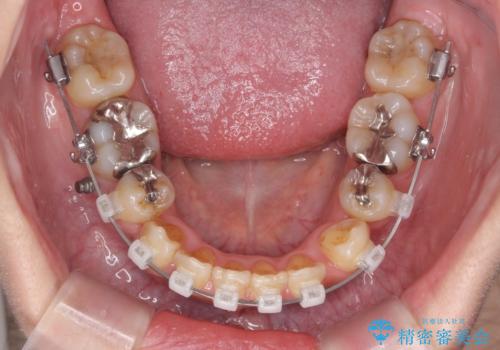

- 八重歯・がたつきのある歯並びの改善を求めて来院されました。

全部の歯が入り切るスペースがなかったため、小臼歯4本を抜去しワイヤーを用いたマルチブラケット矯正を選択しました。

歯並びの改善と共に、歯ブラシがしやすくなった!と喜んでいただくことができました。